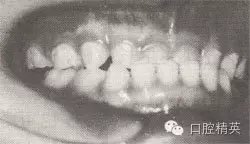

患者,男,4歲,乳牙。磨牙近中關(guān)系。前牙反頜,下頜前突,位置前移。

診斷:乳前牙反頜,安氏Ⅲ類,毛氏Ⅱ¹。

矯治設(shè)計:上頜頜墊式活動矯治器。下頜后退位解剖式頜墊,舌簧推乳上切牙向唇側(cè),調(diào)磨頜墊。

治療時間:1.5個月,乳前牙反頜解除,乳切牙達到正常覆頜、覆蓋。下頜回到正常位置。

圖8-37 安氏Ⅲ類錯頜,乳前牙反頜矯治前后面頜像

矯治前面相

矯治前咬合圖